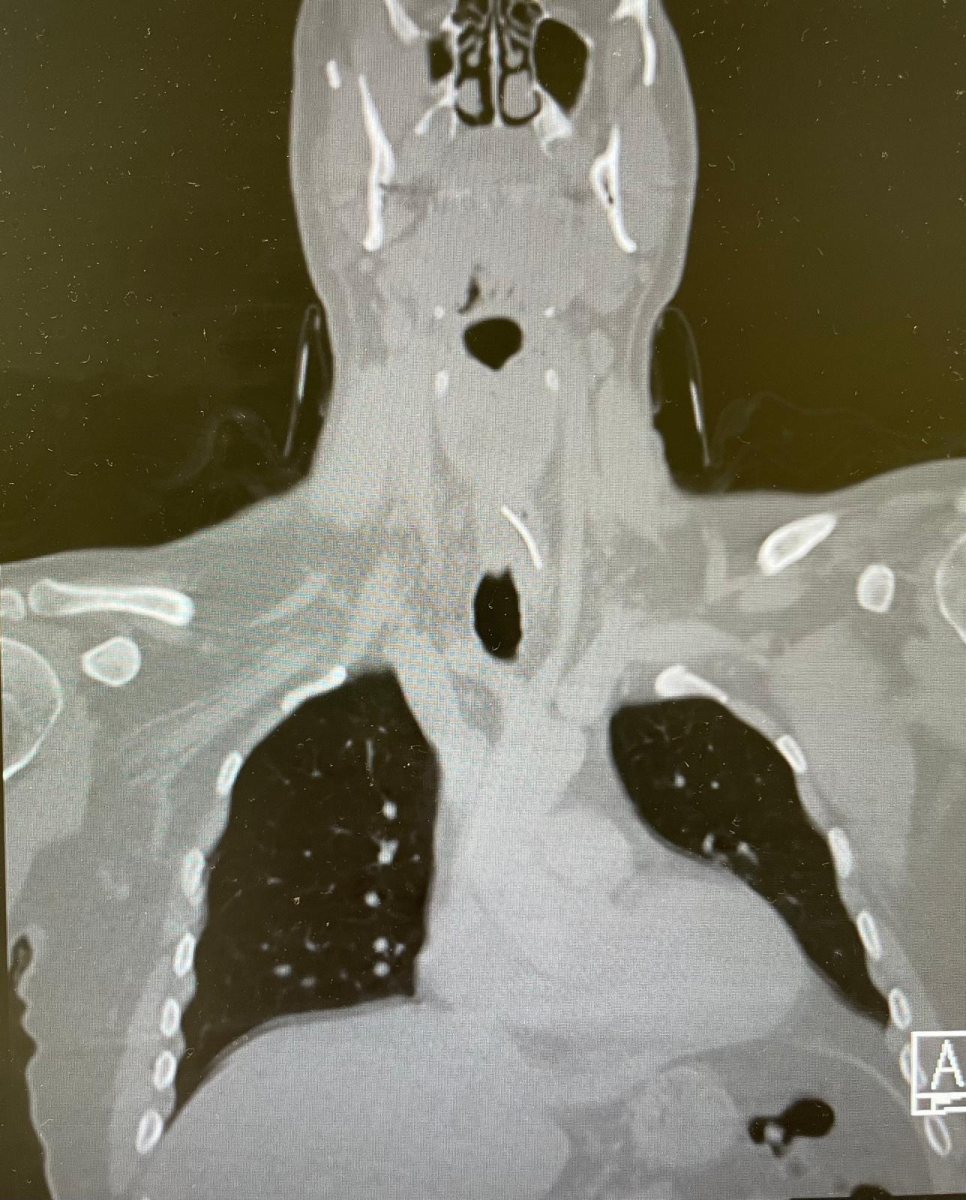

"חיים הגיע אלינו ביום שישי לקראת הצהריים, לאחר שהסתובב שלושה ימים עם תחושת דקירה בבליעה", מספרת ד"ר אור שטריקמן, מתמחה בכירה במחלקת אף אוזן גרון בשערי צדק בניהולו של פרופ' ג'אן איב-סישל . "בשל הרקע של אכילת דג, החשד הראשוני היה שמדובר בעצם תקועה", אומרת ד"ר שטריקמן. "עוצמת הכאב ומשך הזמן שעבר מאכילת הסנדוויץ' היו חריגים, ולכן ביצענו בדיקת CT שהדגימה את הגוף הזר בוושט העליון", מתאר ד"ר אוהד כהן, רופא בכיר ואחראי תחום ניתוחי מיתרי קול וגרון במחלקה.